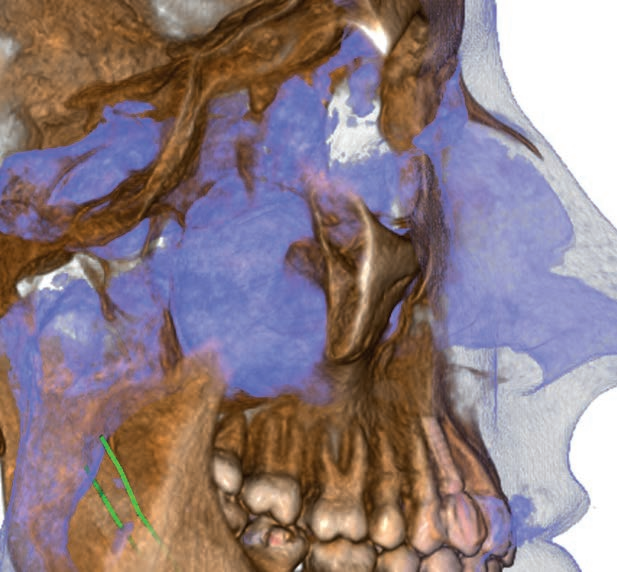

Hyperion X5全景、头颅和X射线体层摄影设备

Hyperion X5不断进化发展,现在头颅及3D拍摄也来到您的面前。这边在整个拍摄过程中快速易用,确保了高分辨率的3D和2D图像、低辐射时间以及实时诊断所需的快速数据处理,改善医患沟通。新的虚拟控制面板简化了拍摄流程,并引入了上颌窦容积检查和正交全景图像的新程序。由于3D传感器模块的自动伺服控制运动,较短的检查时间确保了连续的愉快体验。

3合1,新契机

完整3D:包含牙列和上颌窦范围